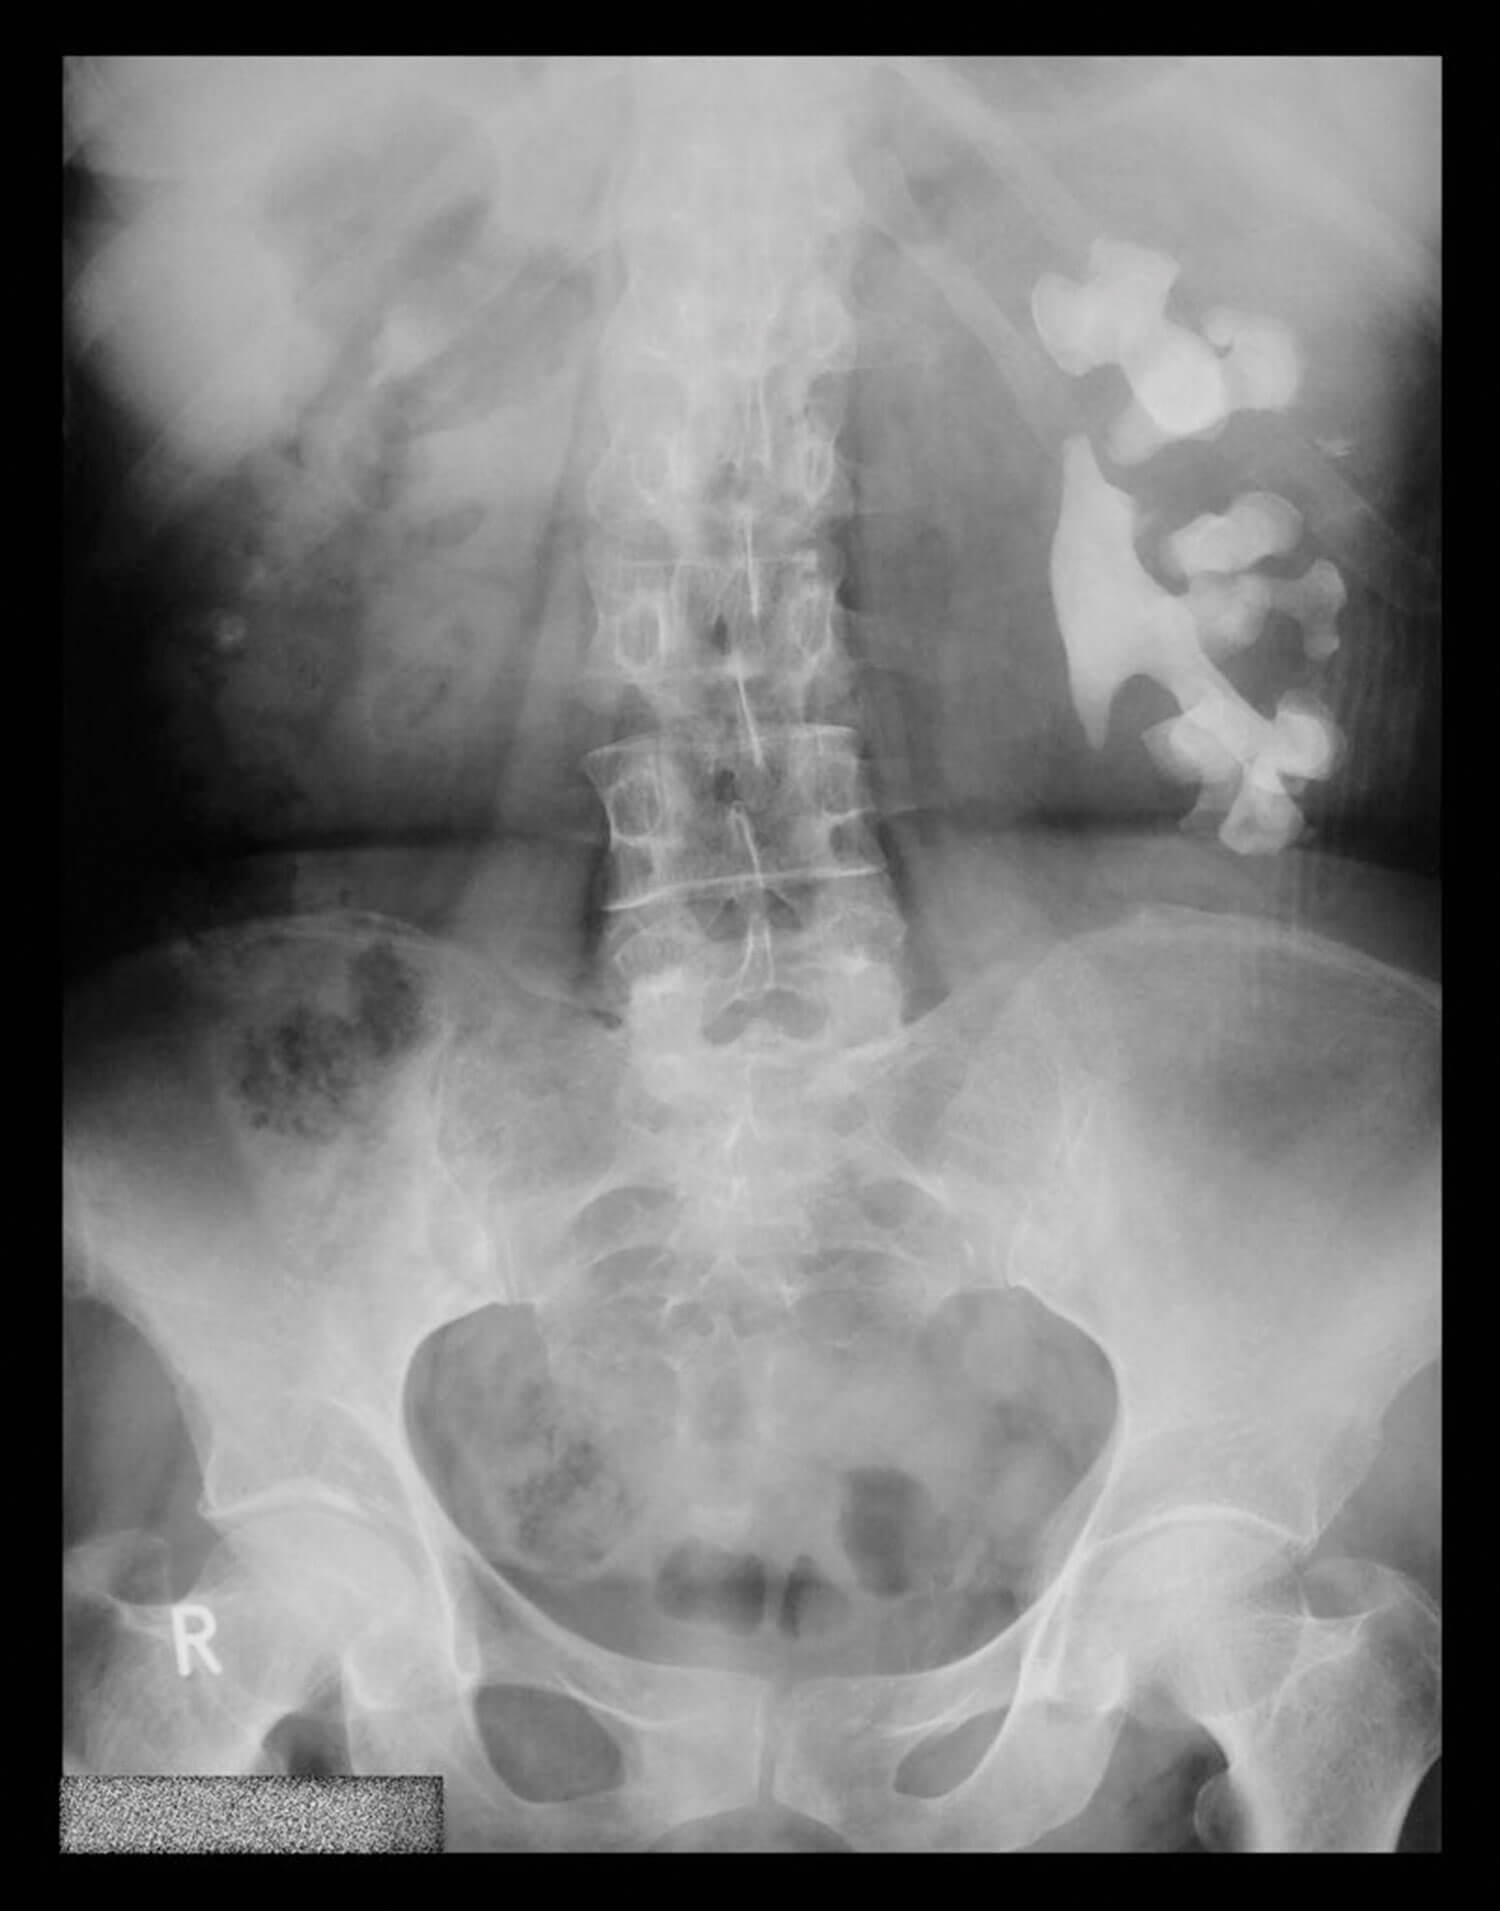

Figure 2

Case 2

1. Uric acid stone (stone analysis is not always possible so it is useful to be familiar with what different stone types look like!).

3. Uric acid stones have low density (200-450 HU).

4. The majority of uric acid stones (but not sodium or ammonium urate) can be dissolved by oral chemolysis. Information on the stone type can be inferred from prior stone analysis, urinary pH measurements and X-ray characteristics.

Oral chemolysis works by raising the pH of urine by using alkaline citrate or sodium bicarbonate (potassium citrate is preferred as sodium may inhibit calcium resorption leading to hypercalciuria and thus calcium oxalate stone formation). Urinary pH should be adjusted to 7.0-7.2 (chemolysis is more effective at a higher pH but this may promote calcium phosphate stone formation). In addition to careful patient follow-up during oral chemolysis, EAU guidelines recommend that patients also monitor their urine pH by dipstick and modify dosage of alkalising medication accordingly as there is direct dose correlation to pH.

Case 3

1. Struvite (magnesium ammonium phosphate) or ‘triple phosphate’ accounts for 70% of Staghorn calculus and usually mixed with calcium phosphate rendering them radio-opaque on plain KUB or CT KUB.

2. Struvite only precipitates at pH >7.2.

3. For struvite stones to develop, it requires an alkaline pH and ammonium in urine which is driven by urease-producing organisms (e.g. Proteus, Morganella, Klebsiella, Enterobacter). Urease from bacteria hydrolyses urea to ammonia and CO2.

4. Urease enzymes catalyse the hydrolysis of urea: H2O + CH4N2O (urea) n 2NH3 (ammonia) + CO2. This in turn leads to ammonium production: 2NH3 (ammonia) + H2O g 2NH4+ (ammonium) + 2OH-.